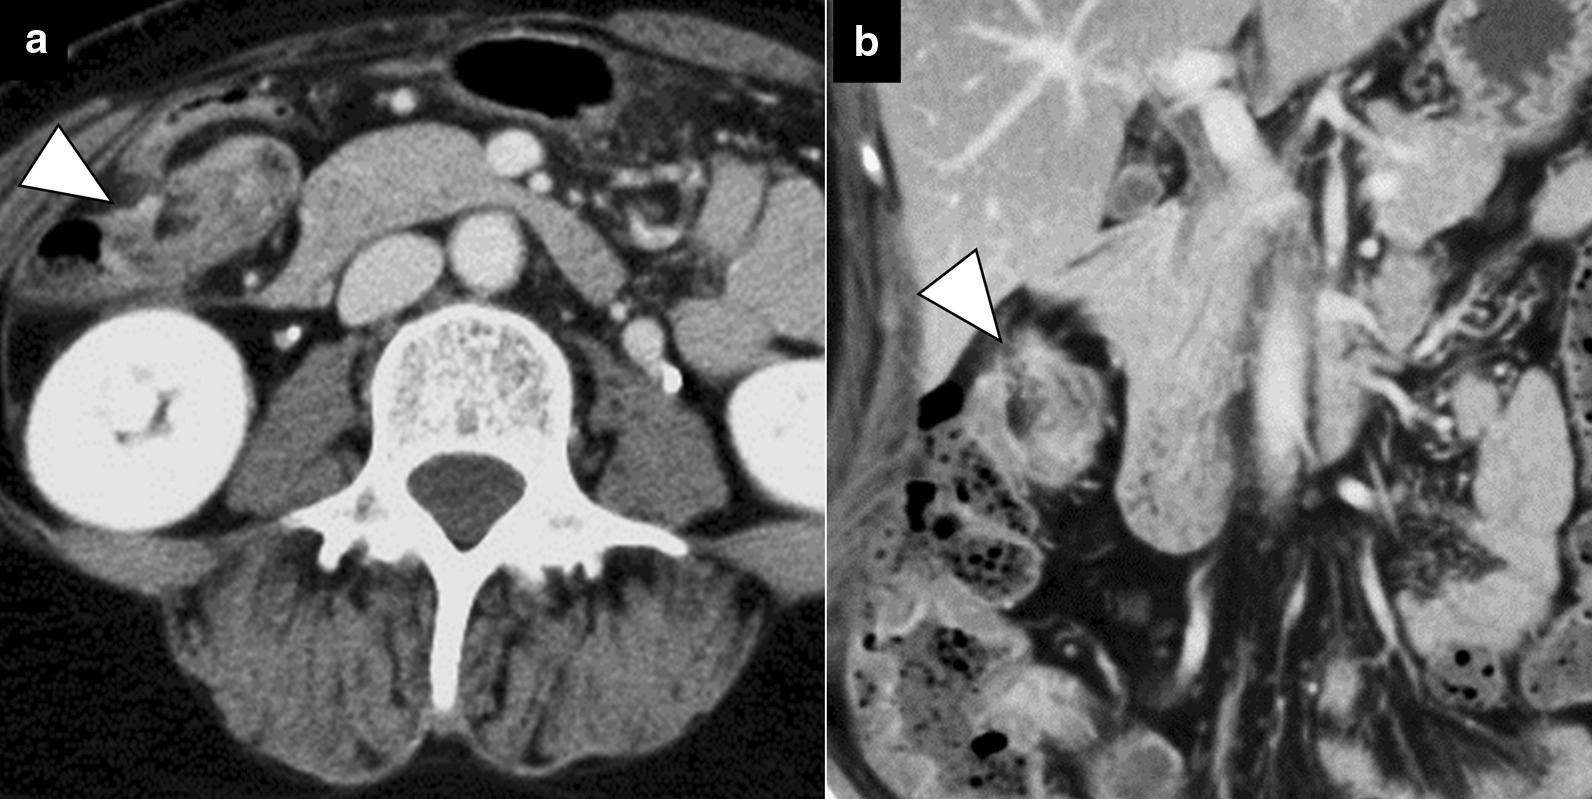

A 53-year-old female with a history of rheumatoid arthritis and thyroid tumor was referred to our hospital. The patient’s chief complaint was abdominal pain for 1 day, and she had no history of abdominal surgery or trauma. Upon admission, she had right abdominal tenderness. Blood tests showed unremarkable results (white blood cell count, 4800/μL; red blood cell count, 4.78 × 106/μL; hemoglobin, 14.8 g/dL; hematocrit, 43.7%; platelets, 20.7 × 104/μL; C-reactive protein, 0.59 mg/dL; creatine kinase, 50 U/L; carcinoembryonic antigen, 2.0 ng/mL; and carbohydrate antigen 19–9, 12 U/mL). Contrast-enhanced computed tomography (CT) revealed intestinal torsion at the hepatic flexure (Fig. 1). A colonoscopy was performed to evaluate the cause of the intestinal torsion, which revealed twisted mucosal folds in the transverse colon but no obvious neoplastic change on the mucosal surface (Fig. 2). The scope could not be advanced past the torsion of the transverse colon, making it impossible to observe the superior colon.

Fig. 1.

Contrast-enhanced computed tomography showing intestinal torsion at the hepatic flexure (arrowheads) (a; axial image, b; coronal image)